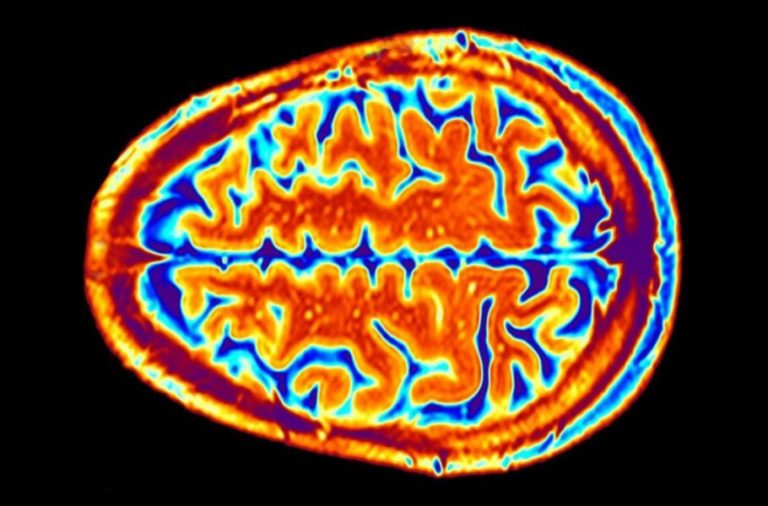

محققان: صافی سطح قشر مغز میتواند ریسک ابتلا به افسردگی را افزایش دهد حتما بخوانید : شرایط فروش ایرانخودرو دیزل ویژه تیرماه 1402 اعلام شد...